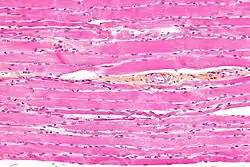

Micrograph of HPS stained skeletal striated muscle (fibularis longus).

Striated muscle tissue is a muscle tissue that features repeating functional units called sarcomeres. The presence of sarcomeres manifests as a series of bands visible along the muscle fibers, which is responsible for the striated appearance observed in microscopic images of this tissue. There are two types of striated muscle: